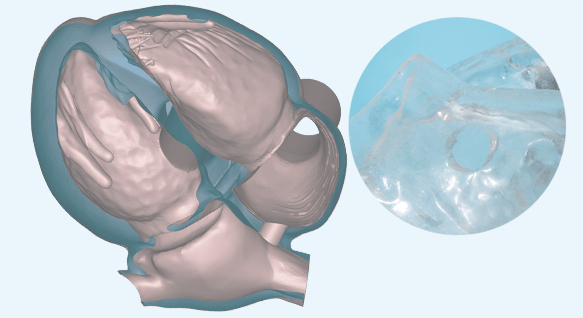

ASD/PFO Closureモデル

心房中隔欠損症を再現した心臓モデルです。透明素材を用いており、心腔内でのカテーテルの動きが外から確認できます。

ASD/PFO Closureモデル

心房中隔欠損症を再現した心臓モデルです。透明素材を用いており、心腔内でのカテーテルの動きが外から確認できます。